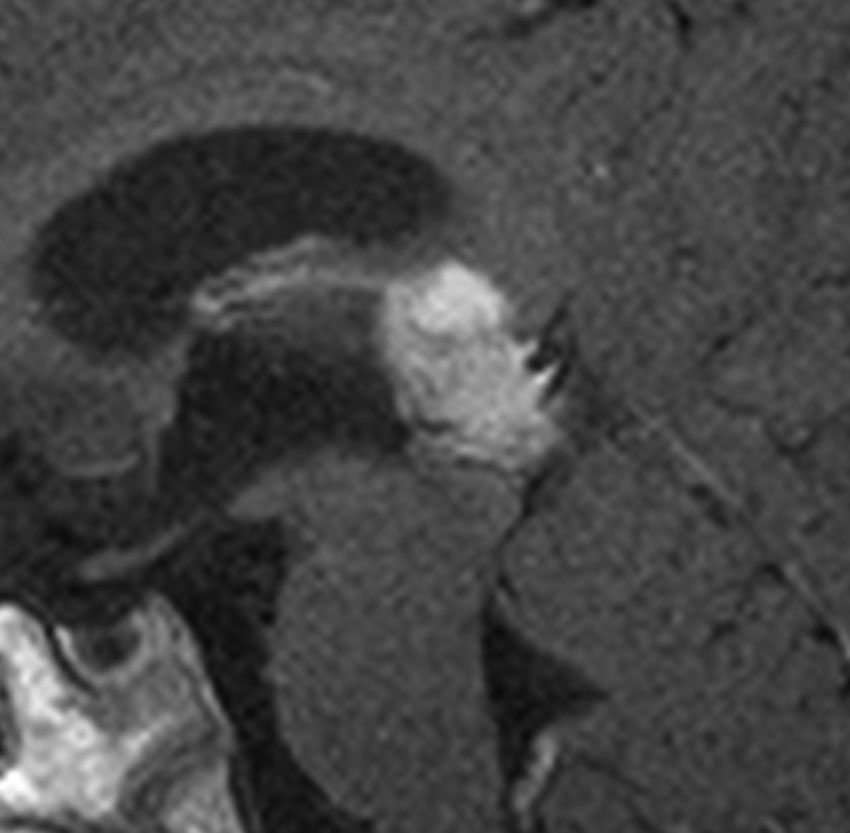

松果体細胞腫の例3(典型例)

これも偶然発見された無症状の女性の小さい松果体細胞腫ですが,ほとんど実質性でのう胞がありません。右はCISSという画像です。中脳の視蓋は圧迫されて変形していますが,中脳水道がまだ閉塞していないのがよくわかります。

左側はMRI血管像です。赤く塗った松果体腫瘍がたくさんの血管とくに静脈に囲まれていて深い位置にあるのがわかります。右は手術後のMRIです。幸い後交連というところも残せたので眼球運動障害(ものが2重に見える)という後遺症は出ませんでした。